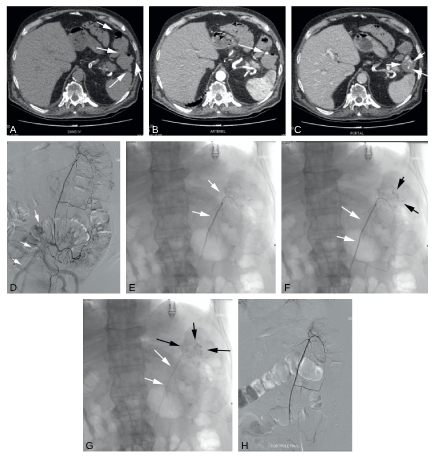

Fig. 7.1 Hémorragie digestive basse chez un homme de 79 ans.

L’examen tomodensitométrique met en évidence un saignement aiguë au niveau d’un diverticule de l’angle colique gauche. (A) Temps sans injection de produit de contraste. Noter la présente de diverticules coliques (flèches). (B) Temps artériel après injection d’un produit de contraste iodé ; Noter l’apparition d’une plage dense au sien d’un diverticule (flèche). (C) Temps portal après injection. Cette plage dense augmente en taille et semble remplir partiellement la lumière colique (flèches). Cet aspect est caractéristique d’une extravation du produit de contraste et permet d’affirmer le saignement actif au temps artériel. (D) Artériographie de l’artère mésentérique inférieure (flèches montrant le cathéter). (E à G) Images successives obtenues après cathéristime hypersélectif de l’artère colique gauche (flèche blanches) montrant une fuite du produit de contraste dans la lumière colique (flèches noires). (H) Contrôle après embolisation à l’aide de particules résorbables (non radio-opaques et non visible sur cette image) montrant l’arrêt de toute extravasation.

Source : CERF, CNEBMN, 2022.